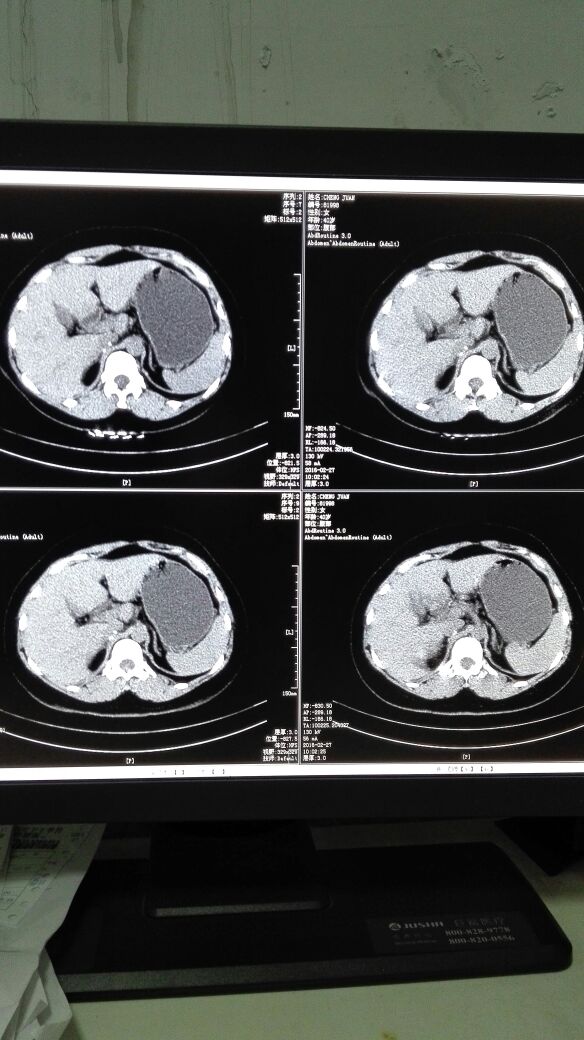

患者女,40岁,医院职工家属。B超体检时发现肝肾间多发囊性占位性病变。行腹部平扫示:右肾上腺区囊性占位,有分割和钙化点,右肾受压下移。诊断意见:右肾上腺囊腺瘤可能性大,建议进一步检查明确。后到市级医院检查并切除手术,病理切片考虑肾上腺囊肿。今腰部不适复查CT片。